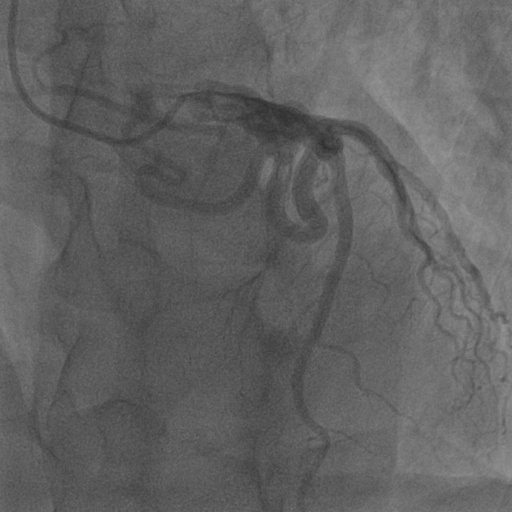

4.1 XACV Dataset

We collect 111 complete records of coronary artery X-ray videos, encompassing the injection, flow through the blood vessels around the heart, and dissipation of the contrast agent. Subsequently, we establish the XACV (X-ray Angiography Coronary Video) dataset. Each video consists of varying numbers of high-resolution coronary artery X-ray images. We invite experienced radiologists to annotate the vascular regions, focusing on one or two frames where the contrast agent is most prominent in each video. The XCAD dataset contains only a single image, and the CADICA video dataset does not provide corresponding ground truth. Therefore, in the following experiments, we conduct all the analyses on our collected XACV dataset and the corresponding GT for each sequence. In Figure 5, we show that compared to other publicly available datasets, XCAD [33] and CADICA [19], our dataset exhibits finer annotations in the vascular regions, providing an advantage for future related tasks. The development and use of our dataset have been approved by our institution’s IRB.